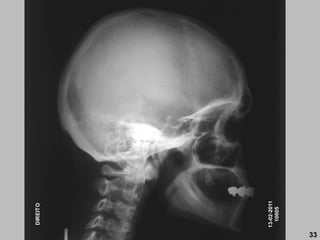

13-02-2011

10005

DIREITO

33